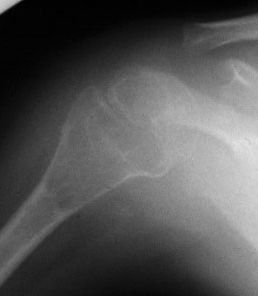

1、攝取病變部位的X線片。X線可以發現骨折以及其他病變,如骨關節炎、椎間盤疾病以及脊椎前移。骨質減少(低骨密度)攝片時可見骨透亮度增加,骨小梁減少及其間隙增寬,橫行骨小梁消失,骨結構模糊,但通常需在骨量下降30%以上才能觀察到。大體上可見椎體雙凹變形,椎體前緣塌陷呈楔形變,亦稱壓縮性骨折,常見於第11、12胸椎和第1、2腰椎。

(1)骨骼X線片:關注骨骼任何影像學的改變和疾病的關係;